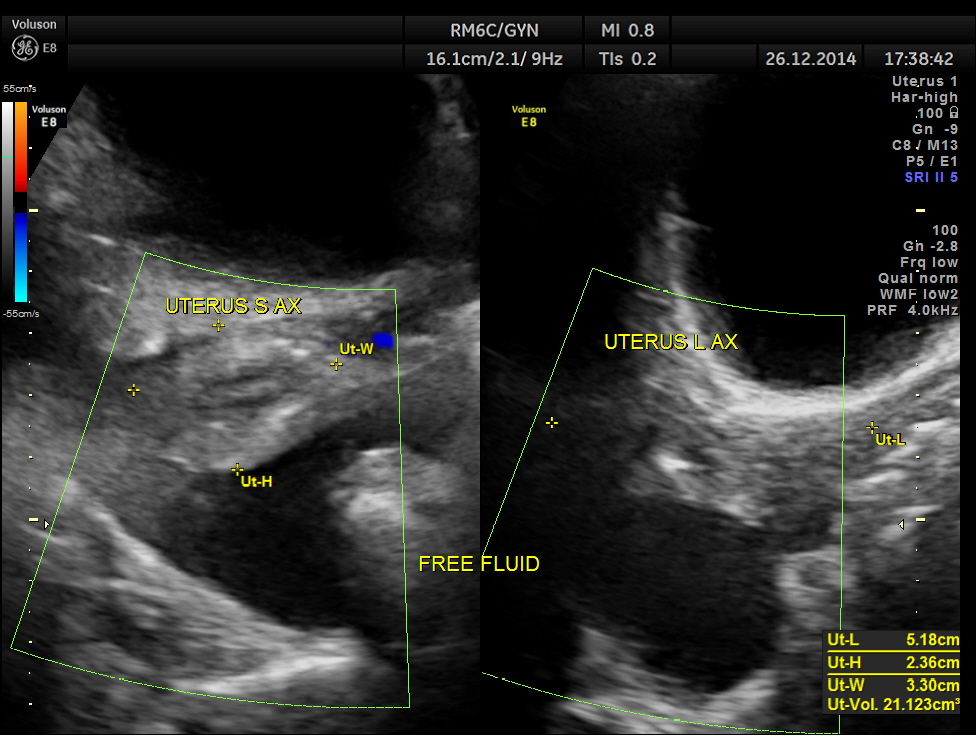

free fluid seen in the abdomen and pelvis , suggestive of possible peritoneal spread of Ca.

This was a case of Carcinoma of the head of the pancreas , causing biliary obstruction and also pancreatic ductal obstruction , with possible peritoneal deposits.